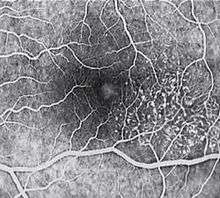

The key fundus findings in macular telangiectasia type 2 involve retinal crystalline—fine, refractile deposits in the superficial retinal layers—may be seen within the affected area.a focal area of diminished retinal transparency (i.e. "greying") and/or small retinal hemorrhages just temporal to the fovea. Dilated capillaries may also be noted within this area, and while this is often difficult to visualize ophthalmoscopically, the abnormal capillary pattern is readily identifiable with fluorescein angiography. Areas of focal RPE hyperplasia, i.e.pigment plaques, often develop in the paramacular region as a response to these abnormal vessels. Other signs of macular telangiectasia type 2 include right angle venules, representing an unusual alteration of the vasculature in the paramacular area,with vessels taking an abrupt turn toward the macula as if being dragged.

Diagnosis of MacTel type 2 may be aided by the use of advanced imaging techniques such as fluorescein angiography, fundus autofluorescence, and OCT. These can help to identify the abnormal vessels, pigment plaques, retinal crystals, foveal atrophy and intraretinal cavities associated with this disorder.

Fluorescein angiography (FA) is helpful in identifying the anomalous vasculature, particularly in the early stages of Type 2 disease. Formerly, FA was essential in making a definitive diagnosis. However, the diagnosis can be established with less invasive imaging techniques such as OCT and fundus autofluorescence. Some clinicians argue that FA testing may be unnecessary when a diagnosis is apparent via less invasive means.